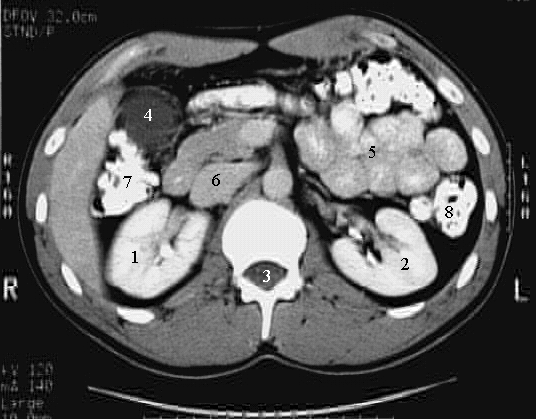

Abdomen: Abdomen Cross: 3 :

1. Right kidney

2. Left Kidney

3. Spinal canal

4. Gall bladder

5. Jejunum

6. Inferior vena cava

7. Hepatic flexure

8. Descending colon.